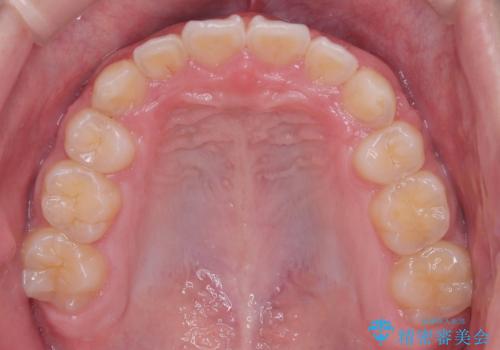

八重歯・歯並びのデコボコとディープバイトを改善した抜歯ワイヤー矯正症例

- 八重歯と咬み合わせを治したいを主訴にご来院された患者様です。

矯正の精密検査の結果上顎左右4番の計2本を抜歯し、審美性に配慮したワイヤー矯正装置(審美装置)を用いて治療を行いました。

八重歯などの歯列のデコボコが綺麗に改善され、患者様にも大変喜んでいただけました。また、咬み合わせが深い「ディープバイト」も併せて改善し、見た目だけでなく機能面でもバランスの取れた咬合を獲得しています。